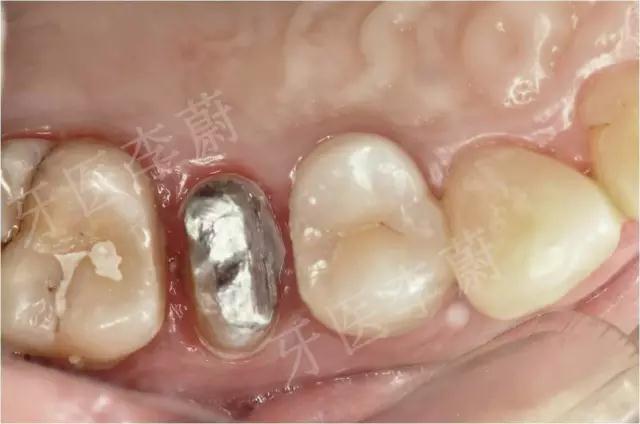

15牙金属分裂桩口内粘接

15牙冠制备中